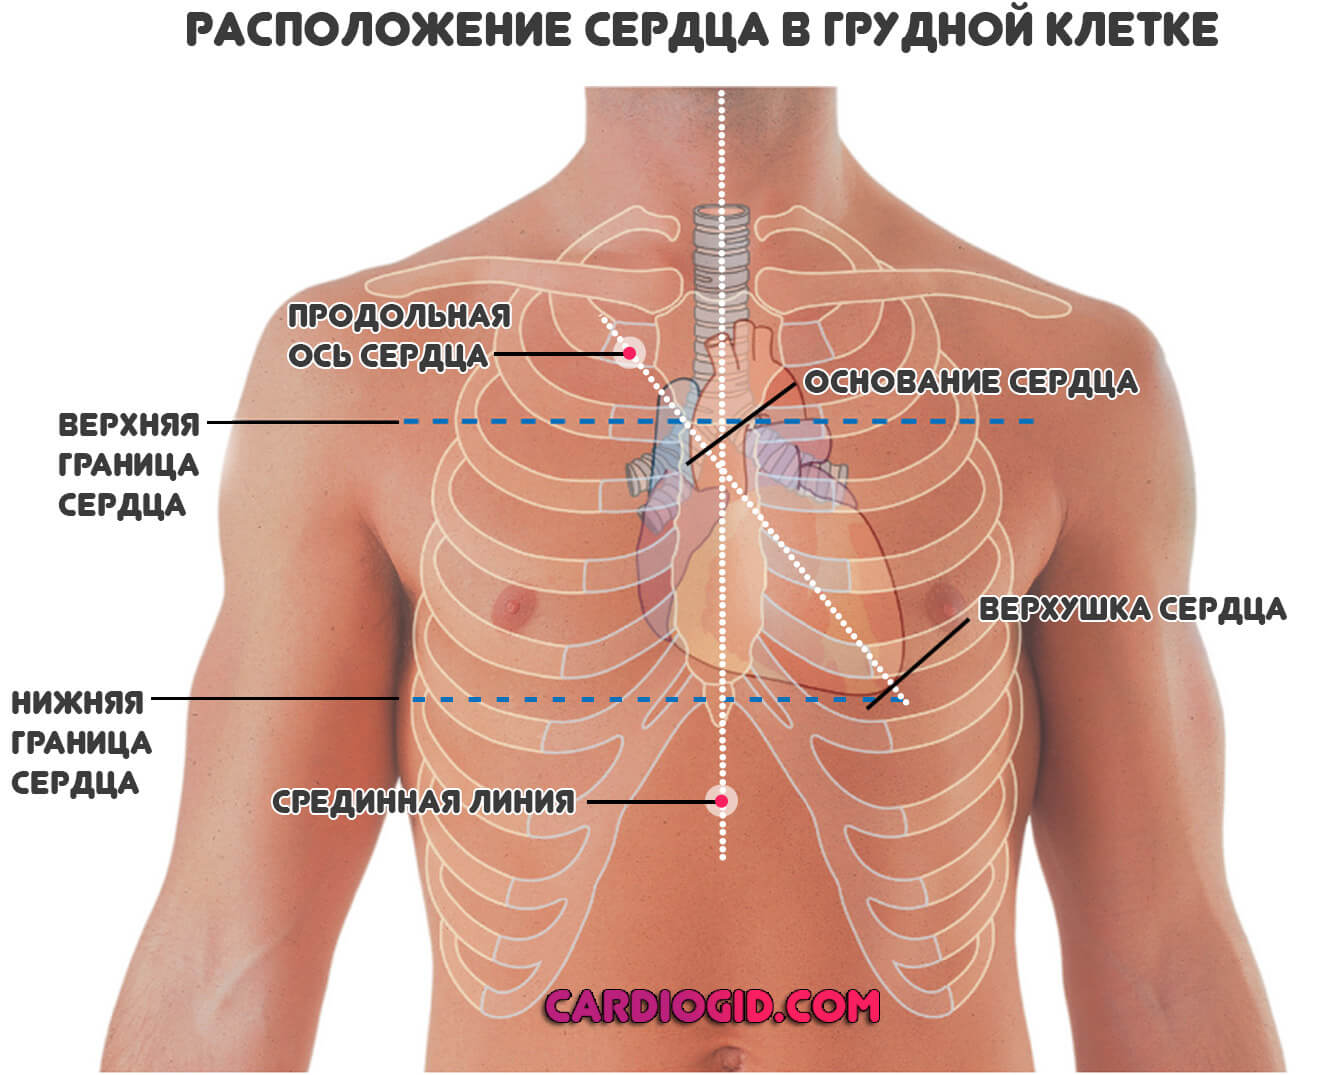

Сердце у человека располагается в грудной полости.

Расположение сердца у человека.

Анатомическое расположение сердца.

Сердце в грудной клетке расположено.

Где расположено сердце у человека анатомия.